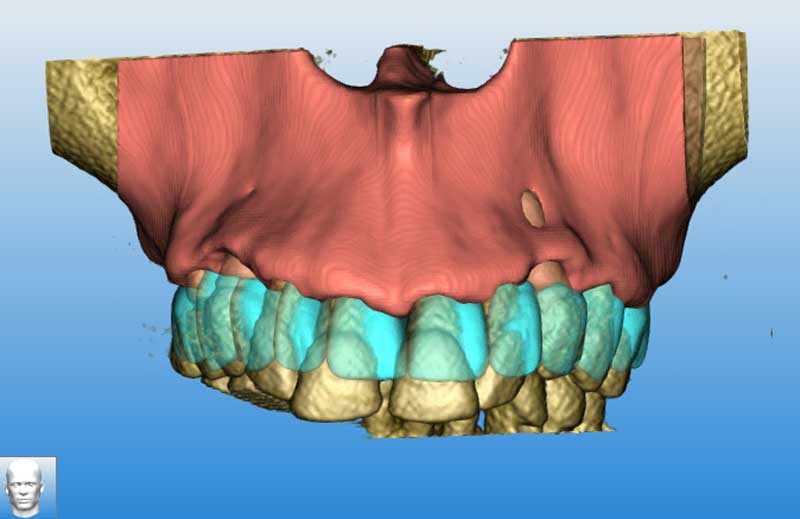

Segmentazione del mascellare, senza i denti

Segmentazione eseguita

Sovrapposizione mockup DCM e Mascellare segmentato 1

Mockup su mascellare segmentato

Visione del mascellare con resettiva effettuato, e progettazione protesica